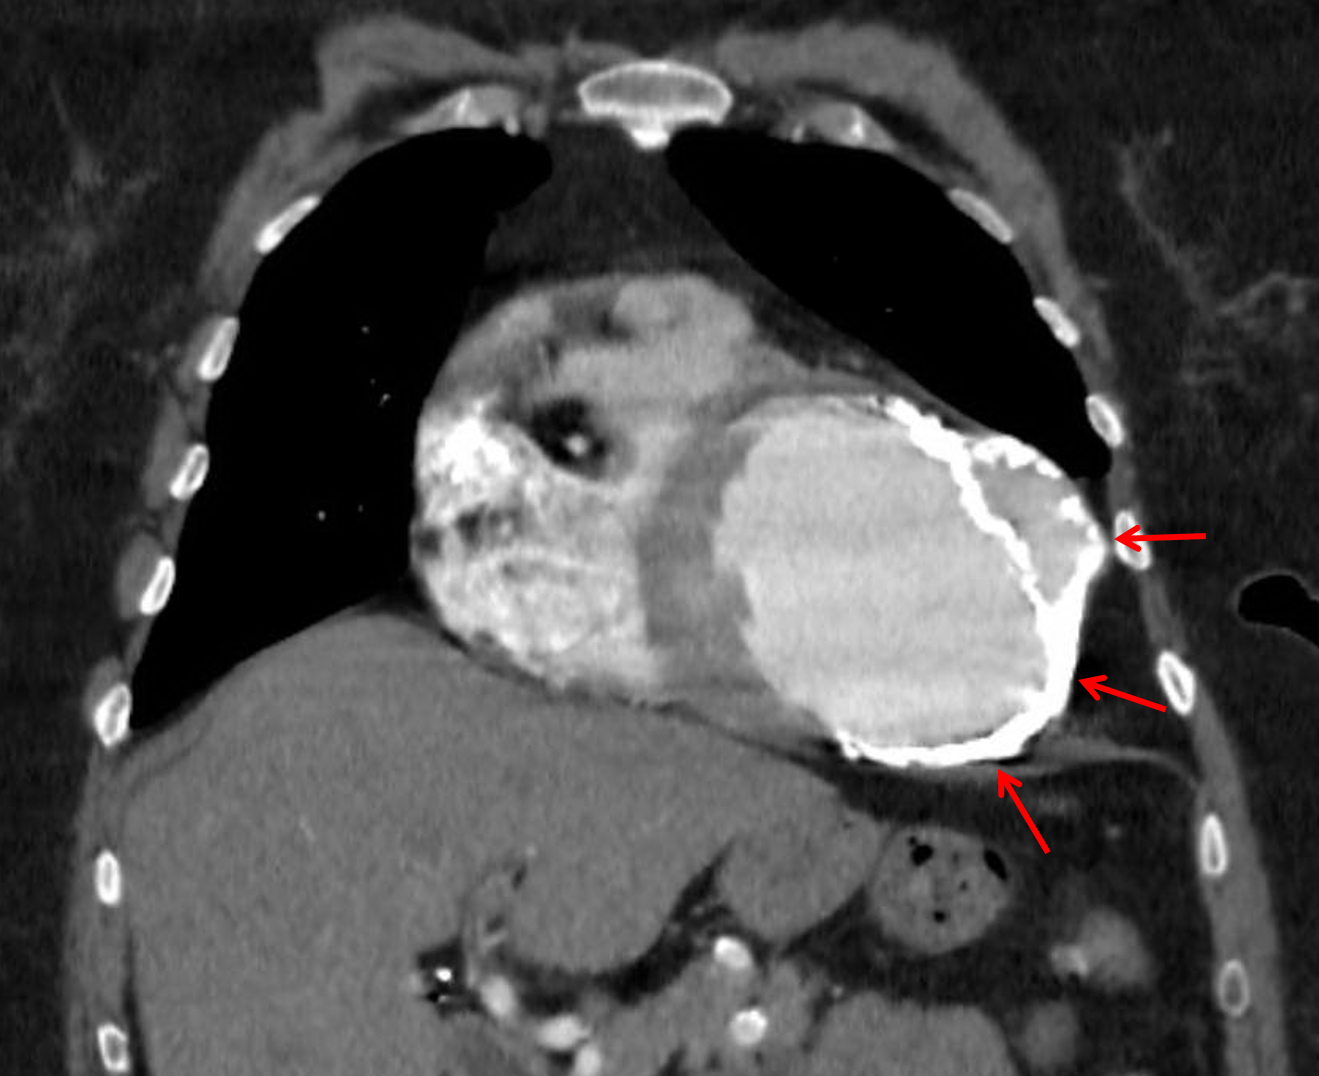

Age: 66

Sex: Female

Indication: Chest pain

CT

Ballooning of the left ventricular apex and apical anterolateral wall with mural calcification and associated partially calcified thrombus at the apex, most suggestive of a true aneurysm.

Multiple partially calcified pleural-based nodules in the left hemithorax. Recommend correlation with prior outside imaging, if available, to document stability. Otherwise consider followup chest CT in 3 months or PET/CT for further evaluation.